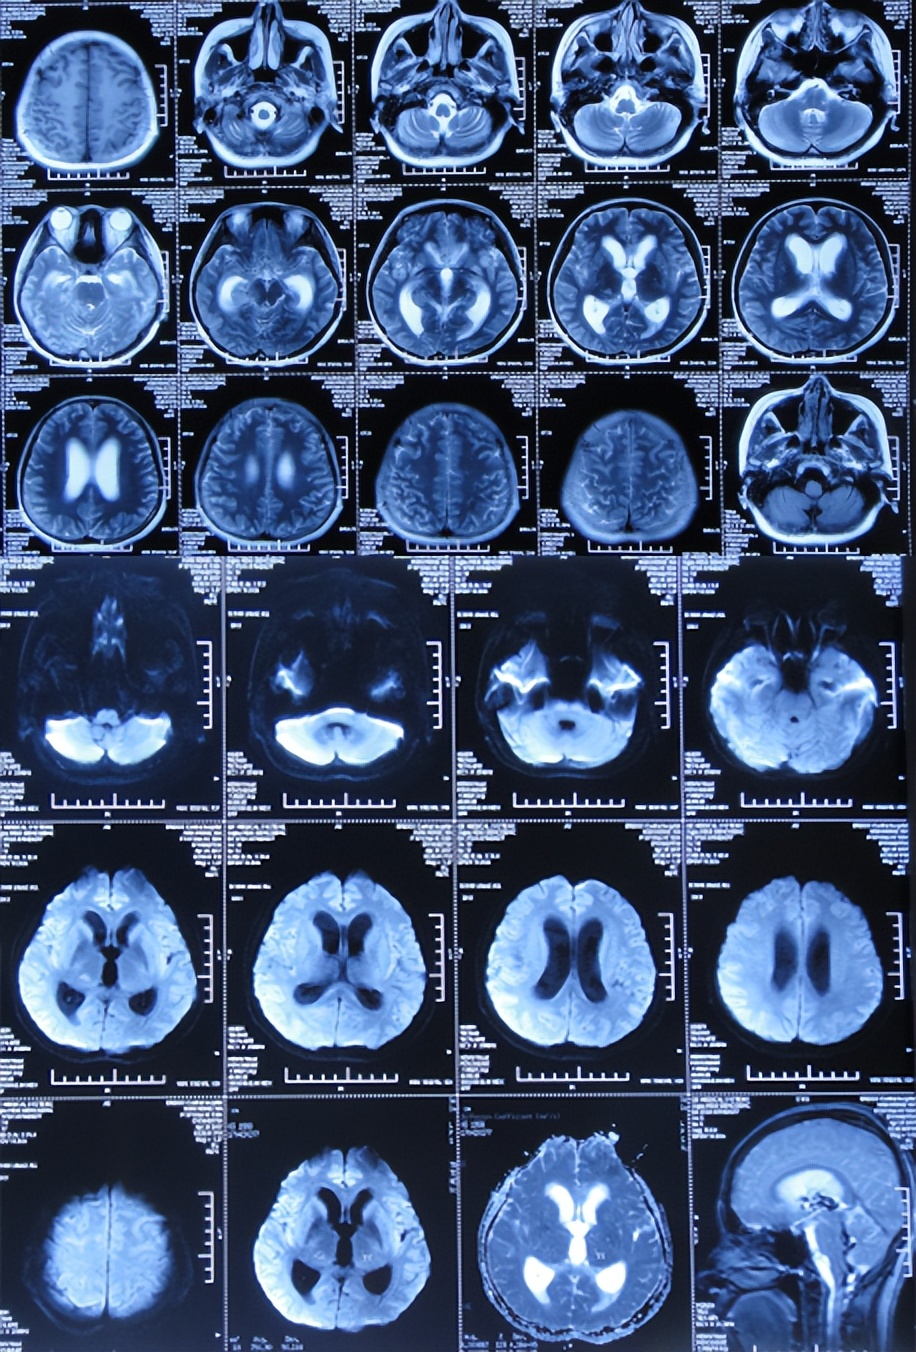

2017年4月26日(入院治疗24天),查脑增强核磁( 图-4 )后,继续给予相关抗感染治疗。

图-4: 2017年4月26日脑增强核磁